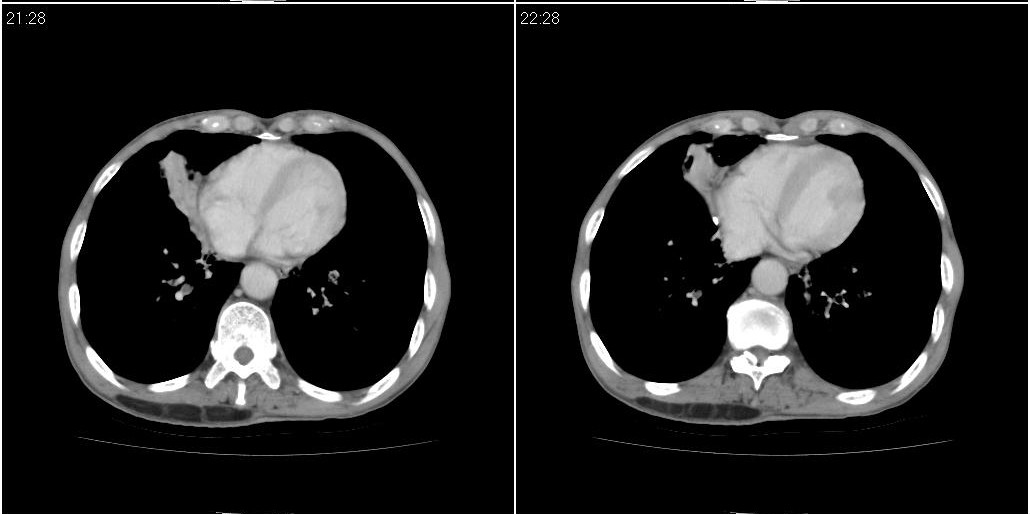

1)右肺中叶慢性炎症并支气管扩张,节段性肺不张。2)两肺下叶支气管扩张。

作者: 草古木子 时间: 2010-3-31 04:37